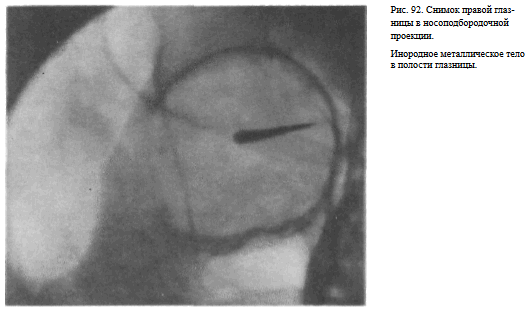

В этой же укладке может быть выполнен снимок одной (правой или левой) глазницы. В таких случаях центр снимаемой глазницы соответствует центру кассеты, и на него отвесно направляют пучок излучения, используя тубус или диафрагмирование пучка излучения с помощью щелевой диафрагмы. Фокусное расстояние—100 см (рис. 88).

Информативность снимка. На снимке хорошо видны вход в глазницу, структура ее стенок, иногда малое и большое крыло клиновидной кости (рис. 89). На снимке в этой проекции могут быть выявлены деструктивные изменения стенок глазницы и инородные тела в ее полости (рис. 90, 91). Для выявления изменений в области верхней стенки глазницы (например, при

На прицельном снимке каждой из глазниц в этой же проекции, как правило, небольшие изменения структуры стенок, а также мелкие инородные тела глаза видны лучше. Такие снимки широко используют в офтальмологической практике (рис. 92).